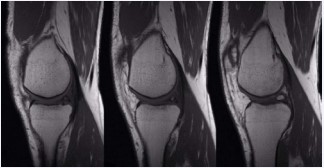

A 44 year old patient, male suffering from rheumatoid arthritis, complaining pain and clamping of the right knee for 5 years during the daily routine activities, with no associated trauma. The patient presents with a history of physiotherapy treatment and two arthroscopic procedures, with no improvement of symptoms. Radiographic examination revealed an image consistent with an intra-articular loose body in the medial compartment, in the topography of the posterior horn of the meniscus (Figure 1). The Magnetic Resonance Imaging (MRI) enabled the identification of bone tissue internal to the posterior horn of the medial meniscus (Figure 2). The surgical treatment was performed by arthroscopy via inter condylar access through the anterolateral and anteromedial portals (Figure 3) to position the optics and visualization of the posterior compartment (Figure 4). We identified the mensicalossicle adjacent to the posterior horn of the medial meniscus (Figure 5) and performed its removal utilizing basket forceps associated with economic resection of the posterior horn of the meniscus, due to the intimate anatomic relation between the two structures (Figures 6,7). The material was subjected to histopathological analysis, which identified fragments of meniscus containing hyaline alterations and metaplastic ossification, apart from a degenerative process, fibrosis, and foci of neovascularization (Figure 8). The patient evolved satisfactorily, with complete recovery of the range of motion and absence of joint locking symptoms, being that his last clinical evaluation was done with 3 months of postoperative. The last X-ray showed the absence of the bone body on the posterior compartment of the knee (Figure 9).

Figure 2: Sagittal MRI cuts showing the ossicle in the posterior horn of the medial meniscus.

meniscal ossicle due to the presence of a lesion in the substance of the meniscus, circular or triangular in shape, exhibiting a hyper signal center in T1 and surrounded by a hypo signal halo. The appearances are consistent with medular bone tissue and cortical bone, respectively. The examination further provides its precise location, approximate dimensions, and allows the identification of associated lesions [1,21]. Treatment tends to be conservative in asymptomatic cases. Patients experiencing pain or history of recent trauma also receive symptomatic prescription medication and physiotherapy. Refractory cases or those with associated lesions must be addressed surgically, with resection of the meniscal ossicle and treatment of the other lesions. Our patient had already been submitted to two artroscopies and persisted with symptoms, and that probably occurred due to the fact that the posterior compartment of the knee was not examined on these procedures. Arthroscopy with intercondylar access [32] associated with posteromedial portal [33] allows for good visualization of the posterior region of the medial compartment, free from blind spots, in addition to protecting the medial femoral condyle from the risk of iatrogenic lesions, hence being a safe and efficient strategy in the treatment of these lesions [32,33]. It is essential when suspecting of a meniscal ossicle to access the posterior compartment of the knee utilizing the arthroscopic technique described above, otherwise the meniscal ossicle cannot be seen if one utilize only the anterolateral e anteromedial portals. So it is very important that the knee surgeons have the knowledge of the existence of this rare pathologic condition that when suspected needs the arthroscopic approach to the posterior compartment.